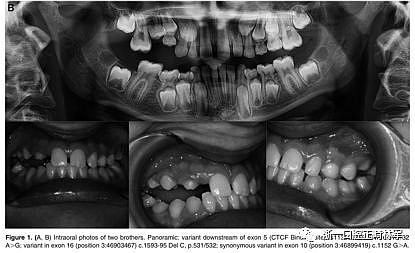

正畸文獻(xiàn)閱讀--原發(fā)性萌出失?。夯旌涎懒械呐R床和遺傳學(xué)研究

正畸文獻(xiàn)閱讀--原發(fā)性萌出失敗:混合牙列的臨床和遺傳學(xué)研究

圖3.(A,B)兩兄弟的口內(nèi)照片。全景:外顯子16中的家族錯(cuò)義變體c.1765 T>C p.589 W>R

屬于2號(hào)家庭的小女兒(2:2)表現(xiàn)出更復(fù)雜的臨床表現(xiàn),缺乏永久性以及暫時(shí)性系列和囊性結(jié)構(gòu)元素的萌出(圖3A,B)。在哥哥(II:1;圖3A,B)中發(fā)現(xiàn)由于包括多顆恒牙的嚴(yán)重的雙側(cè)后牙開合。最后,患者II:1和II:2的母親表現(xiàn)出雙側(cè)上頜第一磨牙和下磨牙的包埋。發(fā)現(xiàn)前磨牙層面沒有咬合接觸(圖3A,B)。